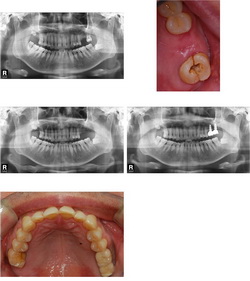

| ¿À¸¥ÂÊ À§¾Æ·¡ ÀÓÇÃ... |

| Àΰø »Ñ¸®¸¦ ½É´Â ¼ö¼úÀÔ´Ï´Ù. »À¿¡ Àû´ç·®ÀÇ ±¸¸ÛÀ» ¶Õ°í Àΰø »Ñ¸®¸¦ ½É¾îµÎ°Ô µË´Ï´Ù. Ä¡¾Æ ÁÖÀ§¿¡ ¿°ÁõÀÌ ½ÉÇÏÁö ¾ÊÀ¸¸é Ä¡¾Æ¸¦ »Ì°í ´çÀÏ¿¡ ¹Ù·Î ÀÓÇöõÆ®¸¦ ½Ä¸³ÇÏ´Â °æ¿ìµµ ÀÖ½À´Ï´Ù. ÀÌÈÄ ¾Æ·¡ Åο¡¼´Â 2-3°³¿ù, ÀÅο¡¼´Â 4-6°³¿ùÀÇ Ä¡À¯±â°£ÀÌ ÇÊ¿äÇÏ¸ç »ÀÀ̽ÄÀ» Çß´Ù¸é Á» ´õ ¿À·£ ±â°£µ¿¾È ±â´Ù·Á¾ß ÇÏ´Â °æ¿ìµµ ÀÖ½À´Ï´Ù. ÀϹÝÀûÀ¸·Î ÀÌ ±â°£ Áß¿¡´Â ÀÓÇöõÆ®°¡ ÈûÀ» ¹ÞÀ¸¸é Ä¡À¯¿¡ ¹æÇذ¡ µÇ±â ¶§¹®¿¡ º¸Ã¶¹°À» Á¦ÀÛÇÏÁö ¾ÊÀº »óÅ¿¡¼ Ä¡À¯¸¦ ½ÃŰÁö¸¸ ¾Õ´Ï¿Í °°ÀÌ ½É¹ÌÀûÀÎ ¹®Á¦°¡ Àְųª ¶Ç´Â ¿©·¯ °³ÀÇ ÀÓÇöõÆ®¸¦ ÀÌ¿ëÇÏ°Ô µÇ´Â °æ¿ì ¹Ù·Î º¸Ã¶¹°À» Á¦ÀÛÇÒ ¼ö ÀÖ´Â °æ¿ìµéµµ ÀÖ½À´Ï´Ù. |

| »À¿¡ ¹¯Çô ÀÖ´Â ÀÓÇöõÆ®¿¡ ´Ù¸¥ ºÎ¼Ó¹°µéÀ» ¿¬°áÇÏ¿© ÀÕ¸ö ¹ÛÀ¸·Î ³ëÃâ½ÃŰ´Â ¼ö¼úÀÔ´Ï´Ù. ¿¹Àü¿¡´Â ¸¹ÀÌ ½ÃÇàÇßÀ¸³ª ¿äÁò¿¡´Â ÀÓÇöõÆ®¿Í ¼ö¼ú Å×Å©´ÐÀÇ ¹ß´Þ·Î ÀÎÇØ 2Â÷ ¼ö¼ú ¾øÀÌ ÇѹøÀÇ ¼ö¼ú·Î ³¡³»´Â °æ¿ìµµ ¸¹½À´Ï´Ù. Á¤È®Çϰí ÃæºÐÇÑ °Ë»ç ÈÄ¿¡ ¼ö¼úÀÇ È¸¼ö¸¦ °áÁ¤ÇÏ°Ô µË´Ï´Ù. |